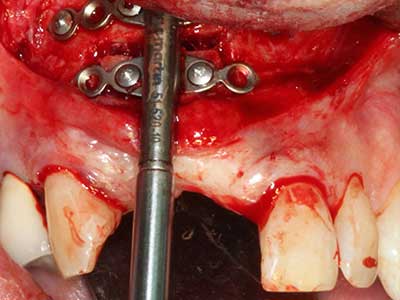

Костната тъкан е не само минерализирана структура, тя съдържа и съществено количество колагенови влакна. Това означава, че тя има не само добра компресивна сила, но и известна степен на гъвкавост, която може да се възприеме като предимство при извършване на костна аугментация. В класическата процедура по разширяване чрез костно разделяне, атрофиралият алвеоларен гребен е разделен надлъжно и внимателно разширен след достигане на подходящата остеотомна дълбочина (Фиг. 13-16), в идеалния случай без допълнително отстраняване на периостеума (Brugnami, Caiazzo et al. 2014, Stricker, Fleiner et al. 2014). Системите с винт и пластини с увеличаване на разстоянието при разширяване са доказали ефективността си при разделяне на двете костни ламели, оставайки под прага на фрактурите. В общи линии, оставащата ширина на костта от поне 3–4 mm е задължителна (Chiapasco, Zaniboni et al. 2006), за да се гарантира добра гъвкавост и достатъчно костно покритие за бъдещото поставяне на импланти. Ако е необходимо, вертикалната остеотомия на едната или двете страни може да подобри гъвкавостта. Комбинацията с допълнителни техники за аугментация, особено в букалната страна, е описана като алтернатива на класическата техника.

Процедурата по разделяне е атравматична и няма голяма загуба на пространство, използвайки пиезотриони, и няма значителна разлика между импланти в разделени челюсти и импланти в алвеоларния гребен без костен дефицит (Chiapasco, Zaniboni et al. 2006, Danza, Guidi et al. 2009). Въпреки това, важно е да има достатъчно и продължително охлаждане, особено при ограничено и дълбоко разделяне, за да се избегне термичен стрес в апикално-остеотомните зони.

Както е показано в миналото, всяка костна хирургия представлява възможна индикация за пиезохирургия. По този начин, за препарацията на подвижни сегменти в остеогенеза (Фиг. 23-25) и остеотомия се използват специални накрайници, без да се застрашава снабдяването с кръв в кресталната зона, което е от съществено значение за успеха и на двете техники (Gonzalez-Garcia, Diniz-Freitas et al. 2008).